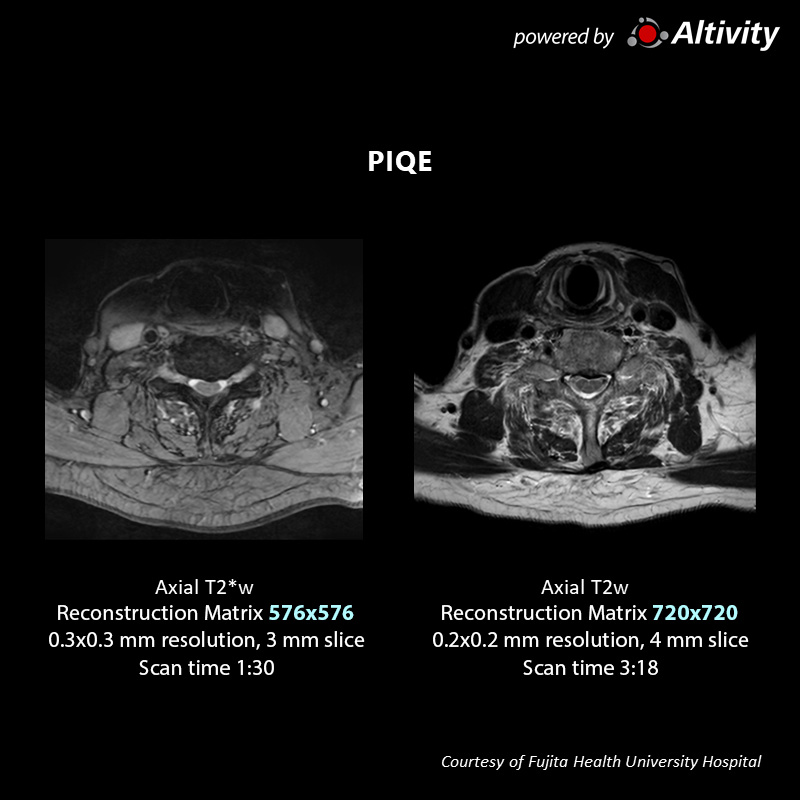

Neuro & Spine

Vantage Galan 3T

Axial FE2D T2

Volunteer image with PIQE adapted to SEEPI DWI sequence.

Structural detail can be more finely captured at three times the resolution with PIQE.

Neuro & Spine

Vantage Galan 3T

Axial FE2D T2

Volunteer image with PIQE adapted to FE2D T2 sequence.

Ringing artifacts are reduced by PIQE reconstruction.